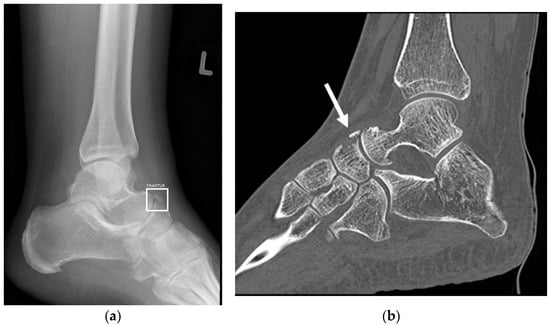

3.6. Fractures in Children